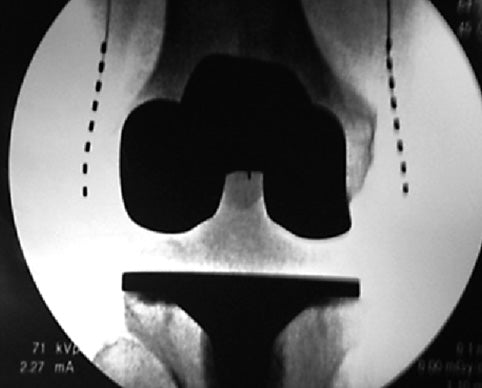

Peripheral joint injections (shoulder, elbow wrist, knee, hip, ankle etc.)